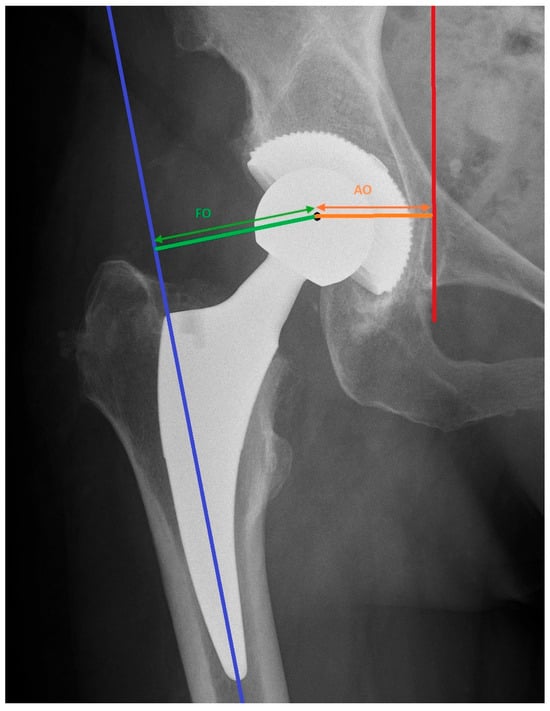

- Liebs, T.R.; Nasser, L.; Herzberg, W.; Rüther, W.; Hassenpflug, J. The influence of femoral offset on health-related quality of life after total hip replacement. Bone Joint J. 2014, 96-B, 36–42. [Google Scholar] [CrossRef] [PubMed]

- Bjørdal, F.; Bjørgul, K. The role of femoral offset and abductor lever arm in total hip arthroplasty. J. Orthop. Traumatol. 2015, 16, 325–330. [Google Scholar] [CrossRef] [PubMed] [PubMed Central]

- Weber, M.; Merle, C.; Nawabi, D.H.; Dendorfer, S.; Grifka, J.; Renkawitz, T. Inaccurate offset restoration in total hip arthroplasty results in reduced range of motion. Sci. Rep. 2020, 10, 13208. [Google Scholar] [CrossRef] [PubMed] [PubMed Central]